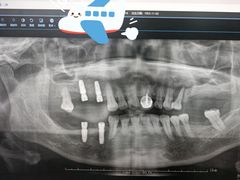

• 牙博士口腔品牌连锁(杨浦店)

• -牙博士口腔品牌连锁(杨浦店)